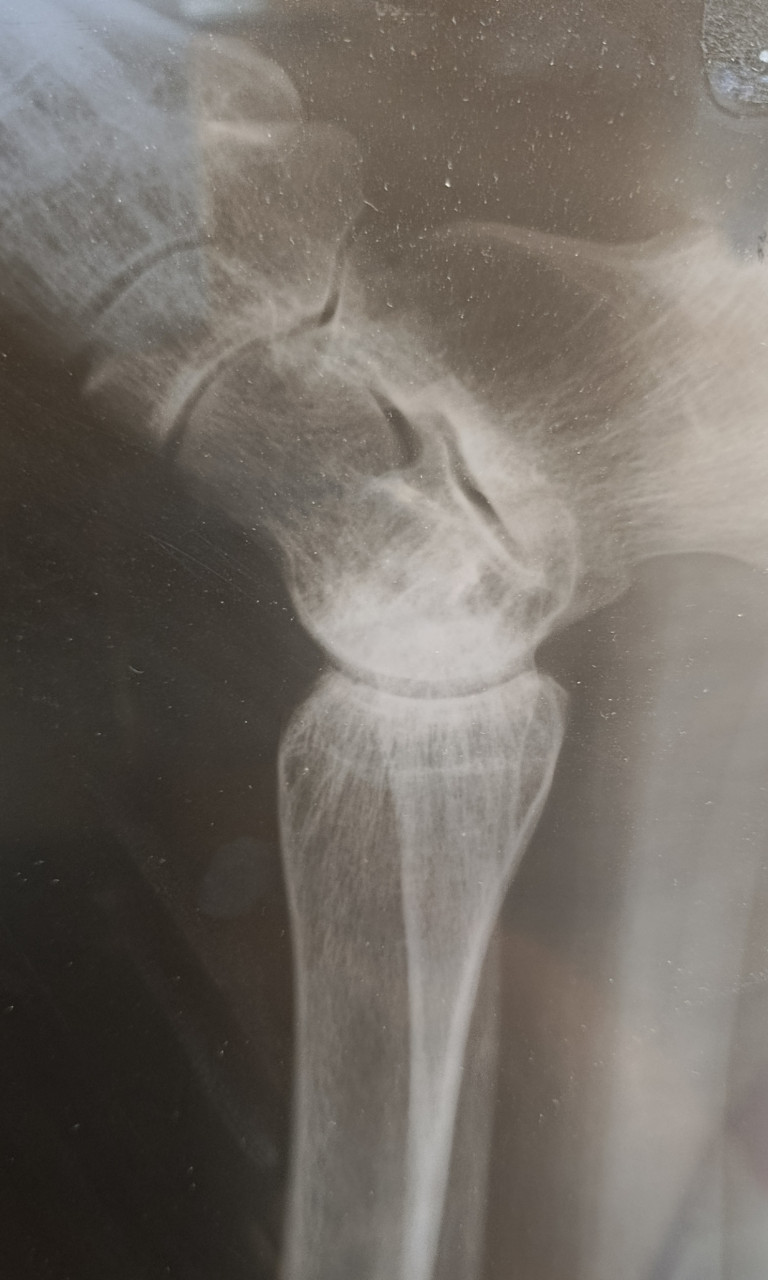

Здравствуйте. У меня перелом, а вот чего именно врач не сказал. Кости или самой лодыжки? Наложили гипс, но он очень стал давить. Пришла на прием к травматологу и его сняли с болью, просто ужас. И отправили домой, вообще без ничего. Сказали купите ортез и носите. Оденете дома. Я на костылях пропрыгала почти 2 суток в эластичном бинте. Скажите пожалуйста, снятие гипса не может повлечь за собой дальнейшее смещение и перелом именно какой части у меня? Спасибо

Здравствуйте. На этом рентгеновском снимке изображение получилось не очень чётким из-за бликов и неравномерного освещения и как я понимаю красное это ноготь, но перелома или выраженной трещины на видимых участках костей я не вижу. Однако для точной оценки нужны как минимум две проекции и осмотр врачом-травматологом. По одному фото плохого качества окончательный вывод сделать нельзя.

Здравствуйте, Владимир Геннадьевич, я поменяла фото в вопросе. Не могли б вы взглянуть ещё раз. Спасибо